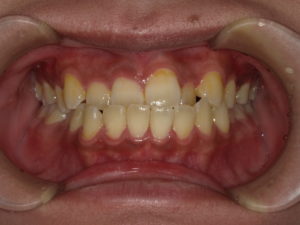

【悪い歯並び2】上顎前突(じょうがくぜんとつ)

user comment….

上顎前突(じょうがくぜんとつ)は、上の顎が前に出ている、いわゆる出っ歯の状態です。

唇が閉じにくくなり、口の中が乾燥しやすいのが特徴です。唾液の分泌量が少なくなり、虫歯や歯周病になりやすかったり、口臭の原因になったりします。